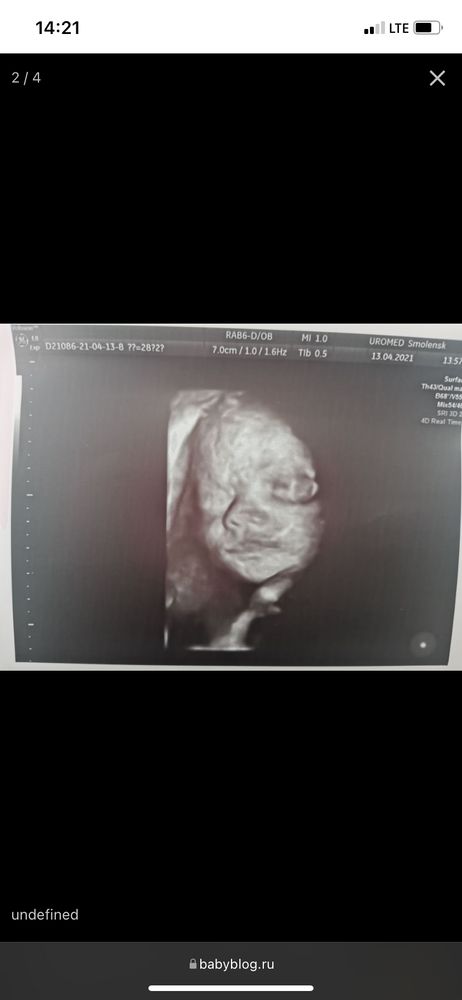

УЗИ 25 недель 🥰

Сходили с мужем сегодня на узи, чета кажется Элиза копия Евы (старшая)😅

А вот протокол УЗИ ☺️ Уже 770гр и все отлично 🙂